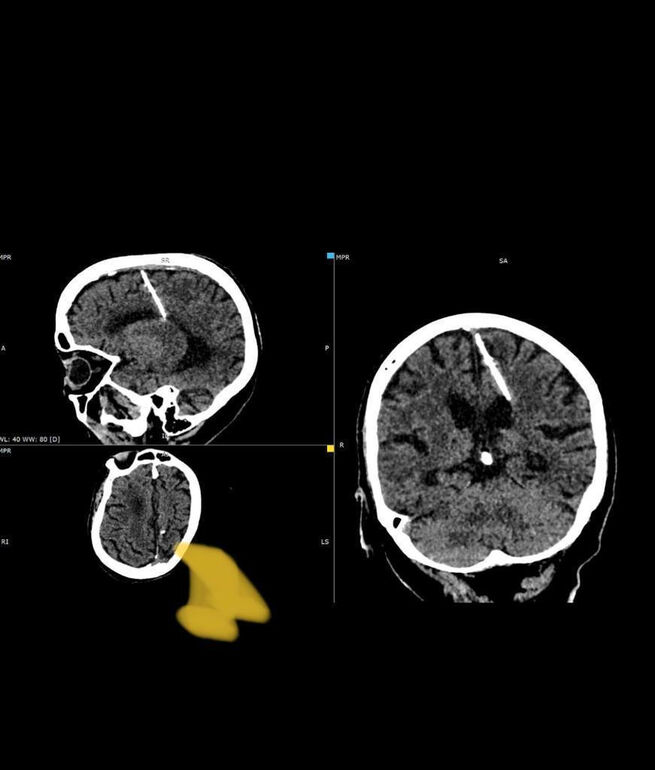

80-летняя жительница Сахалина 80 лет прожила с трехсантиметровой иглой в мозге. Скорее всего, иголка находится там с самого рождения женщины, таким образом ее могли попытаться умертвить в военное время. Этот способ был широко распространен, тонкую иглу вводили в родничок младенца, он быстро затягивался и скрывал преступление, а ребенок умирал. Однако в этом случае женщине повезло, игла проникла в левую теменную долю мозга, но она смогла выжить.

Головные боли ее никогда не мучили. Инородное тело было замечено только во время проведения компьютерной томографии. Извлекать иглу не стали, так как это могло ухудшить состояние пожилой женщины. В настоящий момент здоровью пациентки ничего не угрожает, за ней наблюдает лечащий врач, сообщает региональный Минздрав.

Фото: Telegram / "Минздрав Сахалинской области"